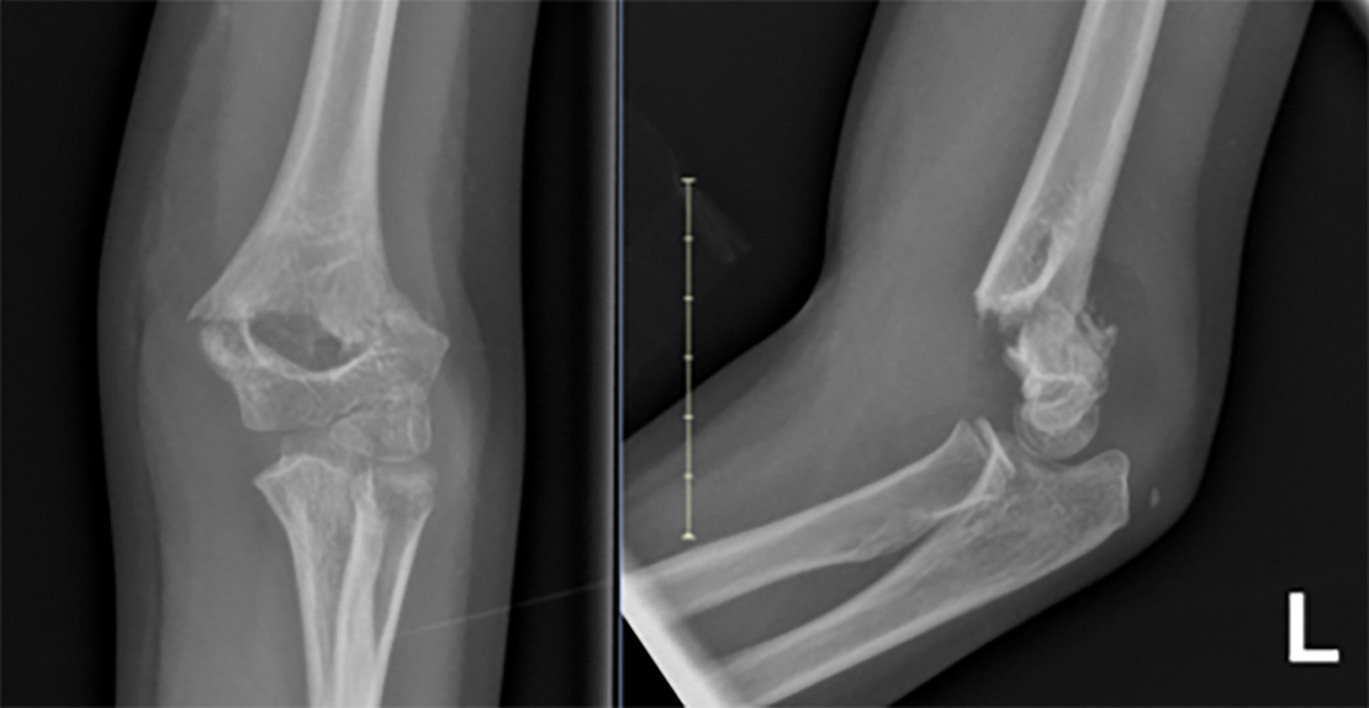

Supracondylar Fracture

Supracondylar fractures most commonly occur between the ages of 2 and 10 years and typically are caused by a fall on an outstretched hand (FOOSH) mechanism with an extended elbow. While distal radius fractures are the most common pediatric fractures, supracondylar fractures are the most common fractures of the elbow in childhood, accounting for 50% to 70% of elbow fractures and roughly 30% of all limb fractures in those younger than age 7 years.9 Unfortunately, they have a high rate of complication, including neurovascular injury, stiffness, cubitus varus, and Volkman’s ischemic contracture.9 Any of the nerves about the elbow may be injured, although the anterior interosseous nerve is the most commonly injured and can be recognized by forearm pain and weakness of pincer grasp.10 Examination is very important because evidence of soft tissue injury, including swelling, tenting, ecchymosis, and/or puckering, is associated with neurovascular compromise and can help determine the speed at which surgical management is needed.11 These fractures can be identified on X-ray as demonstrated in Figure 1. Furthermore, the Gartland classification is used to classify pediatric supracondylar fractures and is described in Figure 2. Management of these fractures has been largely debated and still has great variation.12 The clinical practice guidelines from the American Academy of Orthopaedic Surgeons (AAOS) concluded the only moderate recommendations include nonsurgical immobilization in nondisplaced fractures or posterior fat pad signs and closed reduction along with pin fixation in those with displaced type II and III flexion fractures.13 Given the variation in practice patterns and ambiguity, orthopedic surgery consultation is warranted for these fractures.

Figure 1. Gartland 4 Supracondylar Fracture on AP and Lateral X-Ray |

![]() |

AP: anteroposterior Image courtesy of Matthew Oram, MD. |